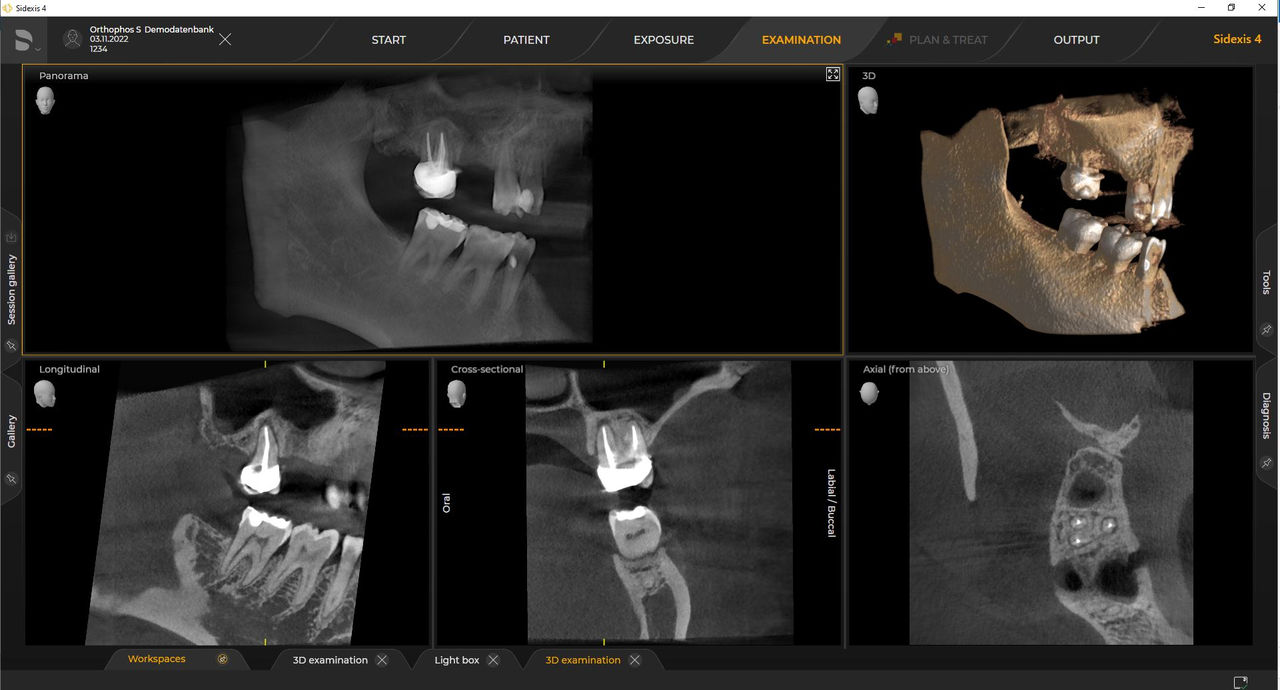

Das hochwertige 2D/3D-Röntgengerät mit umfassendem Leistungsspektrum für jede Praxis. Ob als reines 2D-Gerät oder mit integriertem 3D-Modul – Orthophos S ist ein zuverlässiger Partner und optimiert für alltägliche Aufgaben. Gestochen scharfe Aufnahmen dank CsI-Plus-Sensor und Autofokus. Die automatische Patientenpositionierung zusammen mit dem patentierten Okklusalaufbiss ermöglicht eine einfache und zeitsparende Patientenpositionierung. Für den Einsatz in der Kieferorthopädie ist der Orthophos S auch mit einem optionalen Ceph-Arm erhältlich. Und da Zukunftssicherheit für Dentsply Sirona wichtig ist, kann der Fernröntgenausleger jederzeit nachgerüstet werden.

Mit dem Intelligent Low Dose-Modus erhalten Sie 3D-Röntgenbilder im Dosisbereich einer 2D-Röntgenaufnahme. Im HD-Modus werden während eines einzelnen Umlaufs bis zu 1.400 Einzelbilder aufgenommen und zu einem 3D-Volumen mit bis zu 80 μm zusammengeführt. Der Vorteil für Sie: rauschärmere Aufnahmen in hoher Auflösung.

Dentsply Sirona Röntgengeräte arbeiten exklusiv mit Sidexis 4. Aber die Datenmigration von Sidexis XG zu Sidexis 4 ist sehr einfach. Wir empfehlen den Wechsel zu Sidexis 4, um die vollen Vorteile des digitalen Prozesses mit den neuesten Werkzeugen zu erleben.